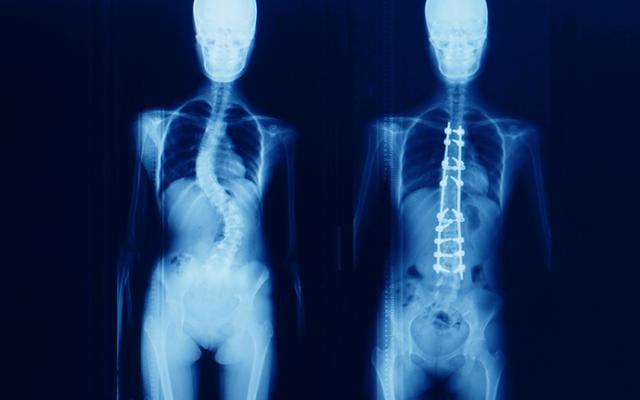

También puede ordenarle unas radiografías de la espalda para mostrar la posición y el tamaño de la curvatura. A la curvatura se le da una medida en grados, denominada ángulo de Cobb. El radiólogo o cirujano pueden comparar radiografías anteriores con las más recientes para determinar si la curvatura está estable o se vuelve más pronunciada.

Cirugía para escoliosis

Según el grado de curvatura, su especialista puede recomendar una cirugía. El propósito de la cirugía es reducir el grado de la curvatura de la columna vertebral y evitar que empeore.

La técnica más común es la fusión espinal, en la que los huesos afectados de la columna vertebral son enderezados y luego se fusionan (unen) entre sí. La curvatura se corrige mayormente por varillas metálicas y tornillos que se ajustan en la columna vertebral.